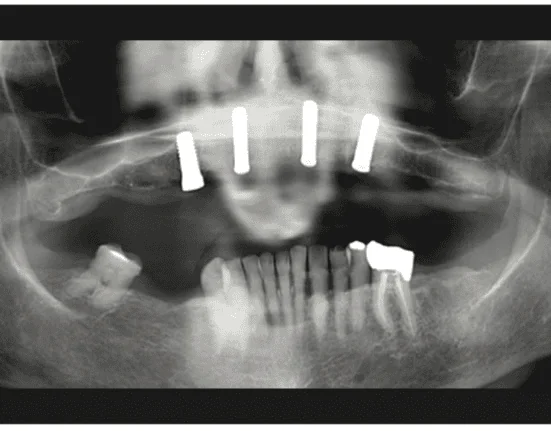

Figure 4. Pre-op panoramic radiograph used to identify vital structures and virtually plan the implant placement.

The clinical examination revealed a fully edentulous maxillary ridge with adequate keratinized tissue (Figure 3). A panoramic radiograph was taken to evaluate the location of maxillary sinuses and the available bone for adequate anteroposterior positioning of the implants (Figure 4). Available treatment options were discussed, and the patient chose the removable overdenture due to finances and less stringent hygiene requirements in comparison to a fixed implant bridge. The surgery was carried out freehand with local anesthesia. Since the patient had adequate keratinized tissue, a mucotome was used to access the bone instead of laying an extended cross-arch flap. Implant osteotomy was done using copious irrigation and manufacturer protocols, and 4 Straumann Pure 2-piece ceramic implants (Straumann) (Figure 5) were placed in the maxillary arch. Intraoperative radiographs were taken to confirm the positioning and angulation of the implants (Figure 6). Final insertion torque of the implants was 35 to 40 N/cm2, and implant stability quotient (ISQ) values of 60 to 78 were measured using the Osstell Beacon device (W&H Dentalwerk). Cover screws were placed over 3 of the 4 implants, and a short healing abutment was placed on the right posterior implant (Figure 7). The implants were left to heal undisturbed. The postoperative panoramic radiograph shows adequate spacing and parallelism of the implants (Figure 8).

Figure 8. Final panoramic radiograph of all 4 implants after placement.